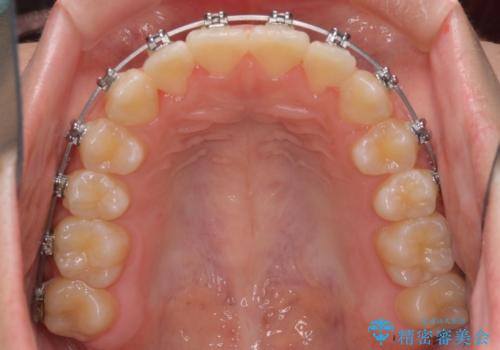

- メタルブラケット

前歯の叢生を解消するスペースを獲得するために上顎左右の親知らずを抜歯し、メタルブラケットにて矯正治療を行うこととしました。

当初は1年半程度の治療期間を想定していましたが、上下の正中を合わせていく過程で奥歯の咬みにくさが続いてしまい、2年以上の治療期間を要することとなりました。